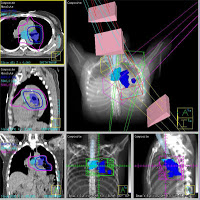

Image guided radiation therapy (IGRT) is the use of frequent imaging during a course of radiation therapy for the purpose of improving the precision and accuracy of delivery of radiation treatment.

IGRT used scans and X-rays to make sure that patient is in the correct position for radiation treatment.

This is another ADVANCE IN RADIATION THERAPY TECHNOLOGY that improves the chance of killing a cancer while reduces risk damaging normal tissues.